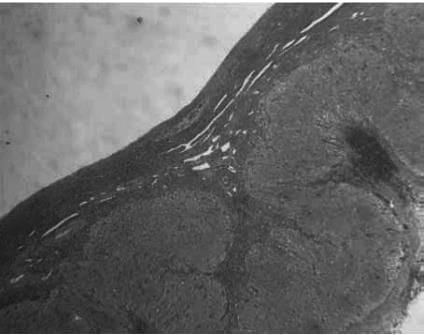

The development of a follicle, from

(a) The primordial follicle is surrounded by a single layer of undifferentiated epithelial cells and is insensitive to gonadotropins

(b) The early antral follicle has well-differentiated theca (immunostained brown) and granulosa cell layers surrounding the developing antral cavity with the oocyte ( Small antral)

(c) The pre-ovular follicle with the oocyte surrounded by the cumulus oophorus with well-differentiated granulosa and theca cell layers (Preovulatory stages)

The histological appearances of the corpus luteum, showing

(a) an active corpus luteum

(b) regression of the corpus luteum with histiocyte infiltration